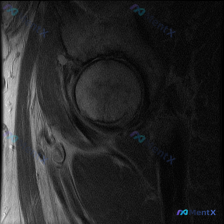

看到一个单层面髋关节冠状位T1加权MRI的病例材料,患者想判断是否有盂唇病变。先放这张影像的观察信息和用户的问题,大家讨论下仅凭这张图能不能诊断盂唇病变? 基础信息: - 图像类型:髋关节冠状位T1加权MRI - 用户提问:是否有盂唇病变? 当前观察到的信息: - 骨性结构:股骨头、髋臼形态正常,关...

最近看到一个髋关节MRI病例,提供的是单帧T1冠状位影像,临床怀疑盂唇病变。但T1序列对软组织的分辨率有限,尤其是对盂唇这样的结构。大家基于这张影像,对盂唇病变的诊断有什么思路?或者有哪些其他的考虑方向?欢迎讨论!